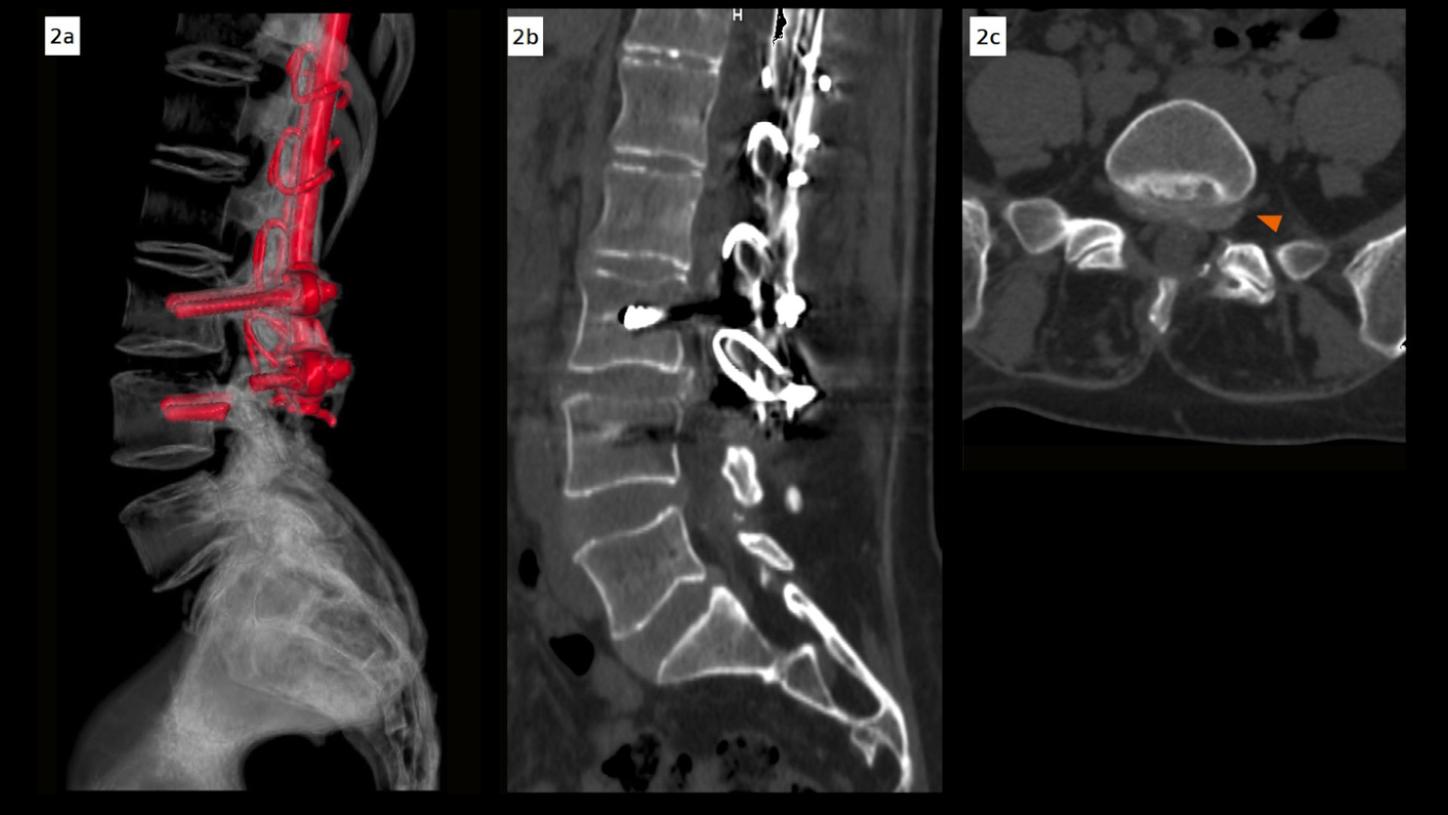

Dual energy CT images with iMAR revealed a fracture of the L4 transpedicular screws and posterior pseudoarthrosis at the L3–L4 level, which were not clearly visible in the previous multislice CT due to extensive metallic artifacts (Fig. 1). Additional findings included diffuse bulging of the L3–L4 intervertebral disc, facet joint nonunion, and posterior fixation hardware contributing to moderate spinal canal stenosis (type C according to Schizas [1] – L3–L4 canal compromise) (Fig. 3). A subarticular and left foraminal protrusion of the L5–S1 disc was also observed, partially occupying the left lateral recess and compressing the exiting nerve root (type D – L5–S1 foraminal impingement) (Fig. 2). The patient is currently being prepared for surgery to address screw failure and pseudoarthrosis. Surgical planning also includes decompression of the L5–S1 nerve root.

Fig. 2: Lumbar spine CT images demonstrating L5–S1 disc pathology. (A) Volume rendering (VRT) reconstruction showing the posterior fixation hardware with evidence of screw fracture at the L4 level. (B, C) Sagittal and axial reconstructions with iterative metal artifact reduction (iMAR) and 140 keV images demonstrate subarticular and left foraminal protrusion of the L5–S1 disc, partially occupying the left lateral recess and compressing the exiting nerve root, consistent with type D L5–S1 foraminal impingement.